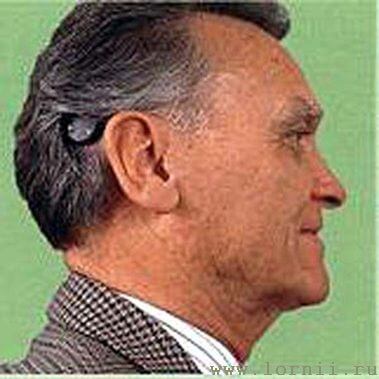

Аудиопроцессор содержит микрофон, элемент питания и электронику. Он располагается снаружи, скрыт волосами и удерживается с помощью магнита (рис. 4, 5).